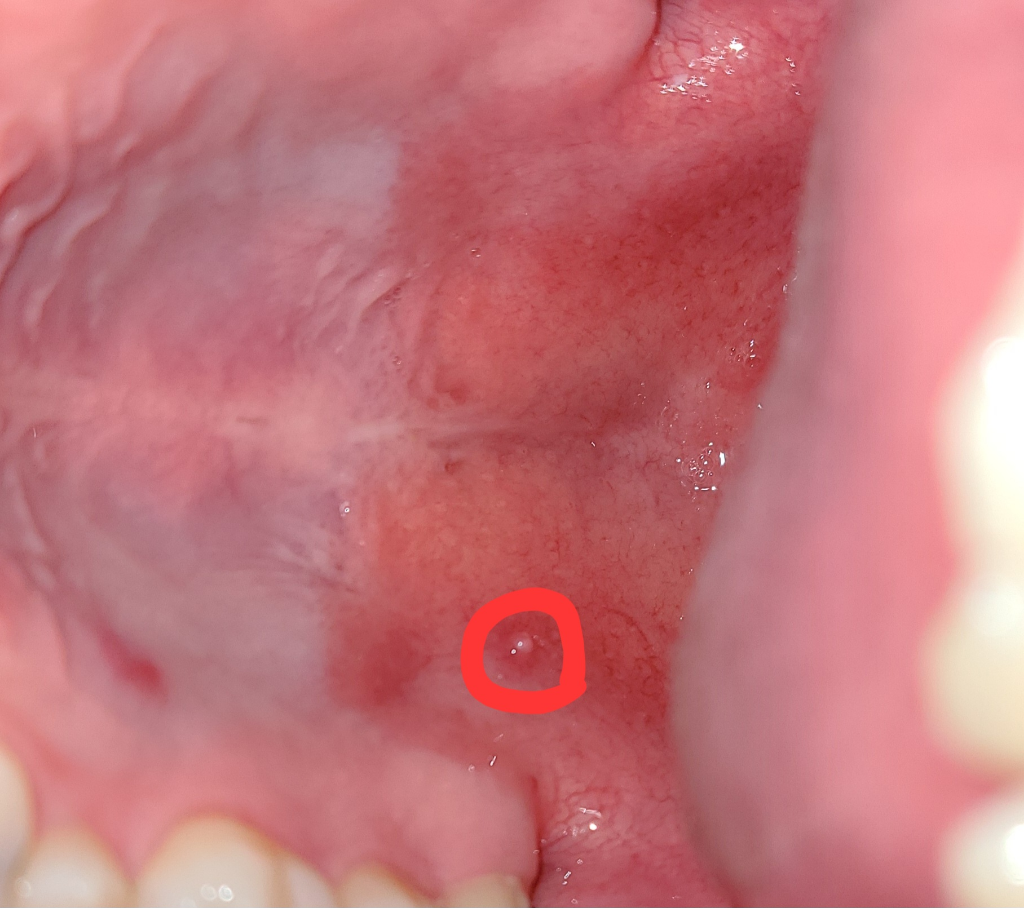

입 천장에 동그란 돌기가 생겼어요

이게 뭔가요?

오늘 밥먹다가 이물감이 있어서 확인해보니 있더라고요

• 1번 째 사진

질문자님께서 말씀하신 대로 입천장의 돌기가 생기는 이유 중에 가장 큰 이유는 스트레스나 수면 환경의 불규칙함으로 인해 나타나는 피로 누적에 의해 발생합니다. 충분한 휴식 및 스트레스를 해소하기 위한 취미활동을 하시면 보통 자연스럽게 호전되기는 하나, 간혹 구내염인 경우에도 발생할 수 있으므로 증상이 악화되거나 혹의 크기가 커진다면 근처 이비인후과나 치과를 방문하여 진료를 보시는 것이 좋겠습니다.